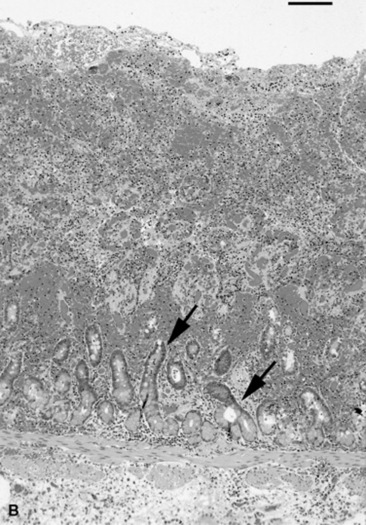

The inflammatory response to invasion often causes massive mucosal necrosis, with loss of mucosal cells and a massive infiltrate of neutrophils and lymphoid cells. Fibrin exudate creates a cast on the mucosal surface of the bowel. The vasculature is exposed to the bowel lumen, allowing subsequent invasion of the bacteria, both pathogens and others, as well as bacterial toxins. The remaining mucosal cells are stimulated to secrete water via the stimulation of cAMP within the crypt cells. Water is also retained in the bowel because of the lack of absorptive cells; the result is diarrhea.

The infection can involve the other layers of the intestine, although it rarely involves the serosa. Still, some diseases such as hemorrhagic fibrinonecrotic duodenitis—proximal jejunitis (DPJ) affect all layers of the intestine. A causative organism has never been discovered to explain DPJ, but the lesion is similar to that seen with clostridial disease in young swine.262 Similar to reperfusion injury, the inflammatory process creates dysfunction that can last for days. Although long-term complications from DPJ have not been reported, animals with severe cases have not survived because of the lack of healing and severe residual inflammation in the bowel wall.262